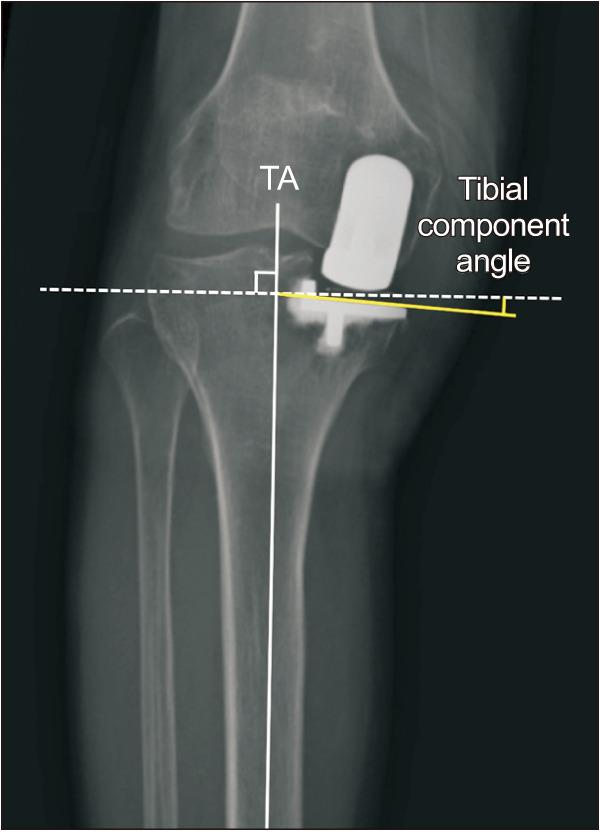

A Novel Technique for Varus Tibial Cutting for Oxford Unicompartmental Knee Arthroplasty.

To reduce the stress on the medial tibial cortex and to decrease the risk of fracture, a varus cut of the tibia appears to be a reasonable alternative to the orthogonal cut by conventional methods. We present a new instrument and procedure, which enables a varus tibial cut for Oxford unicompartmental knee arthroplasty. We used a custom-made, slidable fixator instead of the standard fixator to set the extramedullary rod on the leg. We also made a numeric formula and a chart to arrange the varus cutting angle using the length of the mediolateral shift of the distal end and the longitudinal extension length of the extramedullary tibial rod. A varus cut up to 4.5° can be controlled. This technique is a simple and useful means of obtaining a varus tibial cut for Oxford unicompartmental knee arthroplasty.